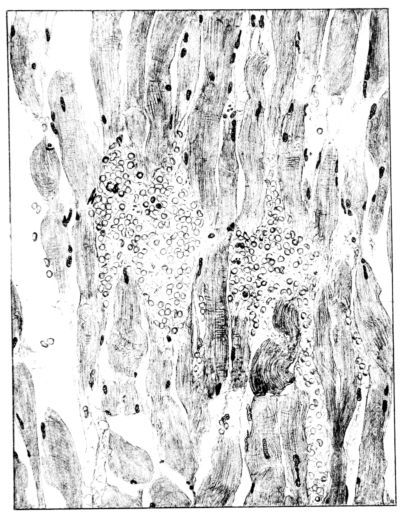

FIG. III. AUTOPSY NO. 90. DRAWING FROM A LESION OF THE TRACHEA (SOMEWHAT OLDER THAN THAT ILLUSTRATED IN FIGURE II). THE MUCOSA IS ENTIRELY LACKING. CONGESTION AND EDEMA ARE THE STRIKING FEATURES IN THE SUBMUCOSA. THE NECROTIZING PROCESS HAS EXTENDED INTO THE MUCUS GLANDS. THIS IS SHOWN IN THE LOWER PICTURE.

The changes are less marked, perhaps, in the trachea than in its finer ramifications. The mucosa is constantly more or less destroyed and large areas, usually focal, are entirely devoid of their epithelial covering. This is replaced by a sparse exudate, composed largely of red blood cells, mucus, a small amount of fibrin, and nuclear fragments (Fig. II). It may dip into the submucosa for a short distance, but usually these indentures are associated with the ducts of the mucous glands into which the inflammatory reaction extends. A more striking feature than the exudate, however, is the edema and the congestion of the submucosa. The loose areolar tissue of the submucosa is spread widely apart, and throughout it distended blood vessels are very conspicuous. Occasionally such a vessel is broken and actual hemorrhage appears in the submucosa. Occasionally, too, the inflammation extends down the duct to the mucous gland itself, and here, also, aplastic inflammatory reaction is evident, inasmuch as the acini now stain intensely red with the cells undifferentiated from each other and specked here and there by broken remains of the dead nuclei (Fig. III). After the disease has continued for a short period, even at the end of five or six days, some regeneration of the epithelial lining may be seen (3) (Fig. IV). But despite this, the acute picture persists, and there goes on, side by side, an attempted repair characterized by epithelial regeneration and the same evidence of acute change. Since the lesion is essentially a superficial one, scars or contractures of any extent are not encountered in the trachea, even in examples of the disease that have ended fatally only after many weeks.[4]